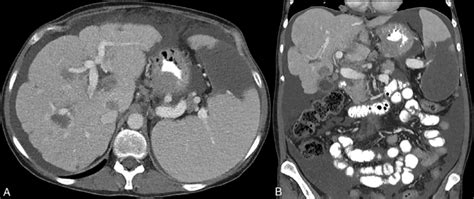

So, what exactly causes this tricky condition we call pseudocirrhosis today ? It’s not one single thing, but rather a collection of different scenarios that can lead to this nodular appearance of the liver. One of the most common culprits is Budd-Chiari syndrome , especially when it’s chronic. Think of this as a blockage in the veins that drain blood from the liver. When blood can’t get out efficiently, the liver can become congested, leading to changes that can look like pseudocirrhosis on imaging. Another significant cause is hepatic vein obstruction from other reasons, like clots or external compression. We also see it in conditions involving portal hypertension , where the pressure in the portal vein (which brings blood to the liver) is abnormally high. This can happen due to problems before the blood reaches the liver, like spleen enlargement, or within the liver itself, even if it’s not true cirrhosis. Certain types of infiltrative diseases , such as some cancers that spread to the liver (metastases) or rare conditions like sarcoidosis, can also create a nodular pattern that mimics cirrhosis. Even severe fatty liver disease in some cases, when it’s really advanced and causes significant inflammation and scarring in localized areas, might present with features that can be confused with pseudocirrhosis. The diagnostic journey to figure out pseudocirrhosis involves a combination of tools. Imaging studies like ultrasounds, CT scans, and MRIs are usually the first step. They can show the nodular texture of the liver. However, imaging alone isn’t always definitive because, as we’ve discussed, it can resemble true cirrhosis. That’s where blood tests come in. Doctors will look at liver function tests, but they also need to investigate the cause . For example, if Budd-Chiari syndrome is suspected, tests might involve looking for blood clotting disorders. If infiltration is a concern, tumor markers or specific blood tests for inflammatory conditions might be ordered. Ultimately, a liver biopsy is often the gold standard for a definitive diagnosis. A small piece of liver tissue is examined under a microscope. This allows pathologists to see the specific changes, confirm the absence of widespread fibrosis of true cirrhosis, and identify any underlying cellular abnormalities or infiltrates that point to the correct cause. This detailed examination is crucial for differentiating pseudocirrhosis from true cirrhosis and guiding the appropriate treatment. The key takeaway here is that this nodular appearance is a sign , not a disease in itself, and finding that underlying cause is paramount.

This is probably the most crucial part, guys: how do we tell pseudocirrhosis apart from true cirrhosis? It’s a big deal because, while they might look similar on the surface (or rather, on the scan!), their implications and management are quite different. True cirrhosis is characterized by extensive and irreversible scarring (fibrosis) throughout the entire liver, disrupting its normal structure and function. This scarring is usually a result of chronic liver injury, like long-term viral hepatitis (B or C), chronic alcohol abuse, or autoimmune liver diseases. The liver becomes hard, lumpy, and eventually struggles to perform its vital tasks. Pseudocirrhosis, on the other hand, presents with nodules and a somewhat distorted appearance, but the underlying architecture is often preserved to a greater extent, and the fibrosis isn’t as diffuse and generalized. Think of it this way: in true cirrhosis, the entire building has been fundamentally reconstructed with faulty materials. In pseudocirrhosis, it might look like there are some major renovations or even some structural damage in specific areas, but the core framework is often intact. The distinction is often made through a combination of clinical suspicion, imaging characteristics, and most importantly, a liver biopsy . While imaging can be suggestive, sometimes the nodular appearance seen in pseudocirrhosis can be quite convincing, mimicking cirrhosis. However, experienced radiologists and pathologists can often spot subtle differences. For instance, the pattern of nodule formation might differ, or certain blood vessels might appear more patent (open) in pseudocirrhosis than in advanced cirrhosis. The liver biopsy is where the definitive diagnosis is often cemented. Under the microscope, a pathologist will look for the extent and pattern of fibrosis. In cirrhosis, they’ll see widespread scarring bands that encircle regenerative nodules, completely disrupting the liver’s normal lobular architecture. In pseudocirrhosis, while nodules might be present, the fibrosis might be more localized, or the regenerative process might be different, and crucially, the diffuse, widespread scarring is absent. The key is that the cause of the nodularity is different. In cirrhosis, it’s typically chronic inflammation and repair. In pseudocirrhosis, it’s often related to issues like blood flow obstruction (like Budd-Chiari syndrome), where the liver tissue reacts to chronic congestion or ischemia, leading to compensatory regeneration and a nodular appearance without the diffuse fibrotic process. This differentiation is super important because the treatment strategies vary significantly. Managing true cirrhosis often focuses on slowing disease progression, managing complications (like ascites or encephalopathy), and in severe cases, liver transplantation. Managing pseudocirrhosis, however, is primarily about treating the underlying cause . If it’s Budd-Chiari syndrome, the focus might be on anticoagulation or procedures to open the blocked veins. If it’s an infiltrative disease, treating that specific condition is key. So, while they share a visual resemblance, understanding the underlying pathology is what truly sets them apart and dictates the path forward for patient care.